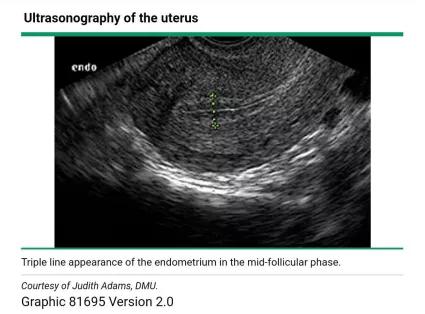

我们常常是用超声来检测月经周期中子宫内膜厚度及质地的变化,具体的测量方法是通过在矢状面的最大前后径水平,对子宫内膜与子宫肌层交界处的回声生成界面,进行测量而获得的厚度。

此后,在雌二醇分泌不断增加的影响下,内膜会增生持续整个卵泡期。这种增生在超声上表现为「三线征」,即子宫内膜表现为低回声,而中间和外基底层则表现为强回声亮线(如下图)。

到了卵泡期末期,测量的子宫内膜厚度为8-12mm之间[1]。在月经中期,子宫颈管可被黏液所扩张,表现为宫颈内的无回声带,这被认为是即将排卵的一个征象。